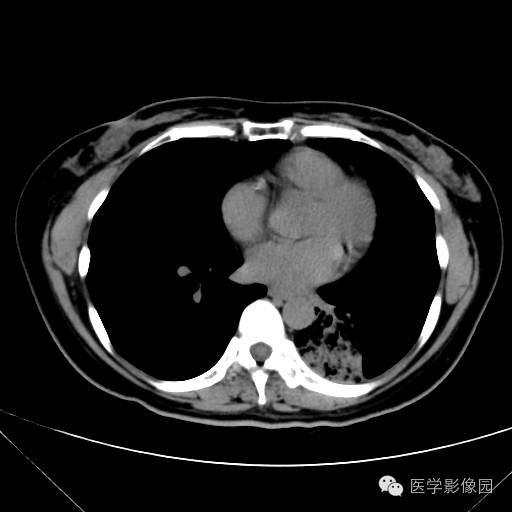

肺叶实变性支气管肺泡癌1例CT影像表现